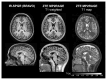

Magnetic Resonance Imaging (MRI) scanners produce loud acoustic noise originating from vibrational Lorentz forces induced by rapidly changing currents in the magnetic field gradient coils. Using zero echo time (ZTE) MRI pulse sequences, gradient switching can be reduced to a minimum, which enables near silent operation.Besides silent MRI, ZTE offers further interesting characteristics, including a nominal echo time of TE = 0 (thus capturing short-lived signals from MR tissues which are otherwise MR-invisible), 3D radial sampling (providing motion robustness), and ultra-short repetition times (providing fast and efficient scanning).In this work we describe the main concepts behind ZTE imaging with a focus on conceptual understanding of the imaging sequences, relevant acquisition parameters, commonly observed image artefacts, and image contrasts. We will further describe a range of methods for anatomical and functional neuroimaging, together with recommendations for successful implementation.